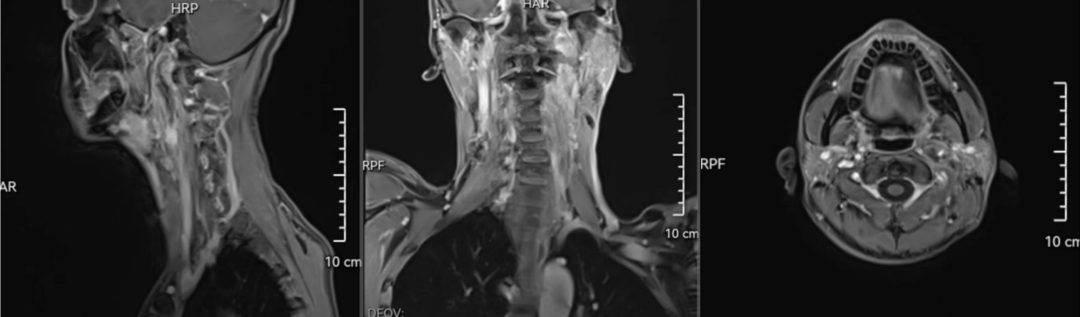

术后磁共振

“该位置的肿瘤非常少见,而此位置这么大的肿瘤,我也是第一次遇到。术中发现肿瘤与颈内动脉,颈外动脉,腮腺,迷走神经及咽后壁等黏连紧密,通过细致分离肿瘤与周边组织的黏连,保证了肿瘤完整切除的同时又维护了正常的生理结构及功能,经过口腔—颌面外科的通力协作,防止了腮腺瘘等并发症的发生。”赵明飞说。

1月13日这天,历时短短2个小时,王和功主任、赵明飞副主任,口腔科杨伟副主任,顺利将患者的肿瘤完整切除,术后患者症状改善,吞咽功能得到好转,无并发症发生。